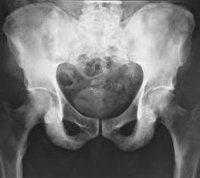

Рентгенография таза

Рентгенография таза. Рентгенологическое исследование для оценки состояния подвздошной, лобковой и седалищной костей, крестца, копчика и тазобедренного сустава. В травматологии это выполняется, когда есть подозрение на перелом таза и остеомиелит, в гинекологии это используется, чтобы идентифицировать узкий акушерский таз. В других отраслях медицины его можно назначать при нарушениях развития, новообразованиях, воспалительных процессах в костях таза и некоторых других патологиях. В плановом порядке, это выполняется после специальной подготовки; во время экстренного обучения обучение не требуется.

Рентгенография костей таза в травматологии назначается при подозрении на остеомиелит и переломы костей таза. Кроме того, эта диагностическая процедура проводится у всех пациентов с тяжелыми сопутствующими травмами. В гинекологии методика позволяет выявить узкий таз у женщин, планирующих беременность. В других областях медицины проводятся исследования воспалительных процессов, доброкачественных и злокачественных опухолей, пороков развития, других заболеваний и состояний, которые могут сопровождаться повреждением костей таза.